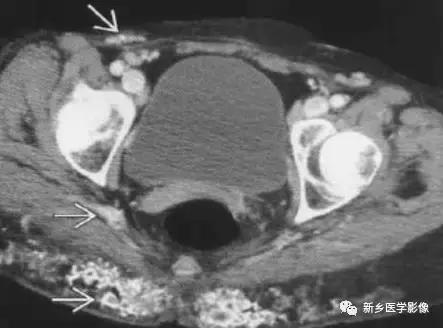

主要表现为皮下组织钙化,多合并结缔组织症(如硬皮病、CREST综合征、系统性红斑狼疮、皮肌炎)